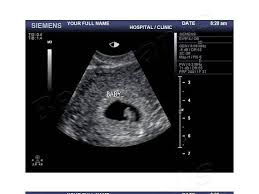

Your baby s heartbeat should be between 90 110 beats per minute bpm at 6 to 7 weeks. Finding a fetal heartbeat on a handheld doppler can take even longer. If you are at least eight or nine weeks along at your first prenatal visit your doctor or midwife may use a fetal doppler or a fetal doppler stethoscope to pick up the sound of your baby s heart beating. Once at 9 weeks.

Discussion in pregnancy first trimester started by amz0109 feb 7 2012. It will be about 170 beats per minutes by this time a rate that will slow from here on out.Source : pinterest.com